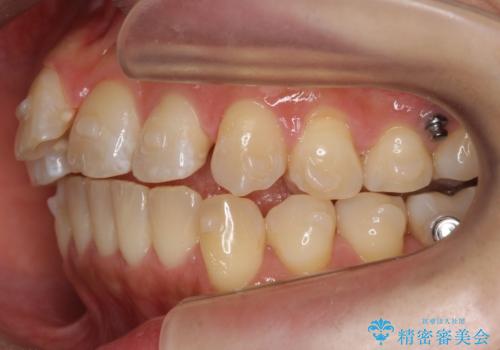

- 前歯の突出を主訴に来院。

上の奥歯を後ろに下げて治療をしました。

矯正用のミニスクリューを使用しています。

上の前歯もIPR(エナメル質をわずかに削る処置)を行っています。